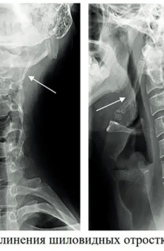

Боль в горле или синдром удлинения шиловидных отростков